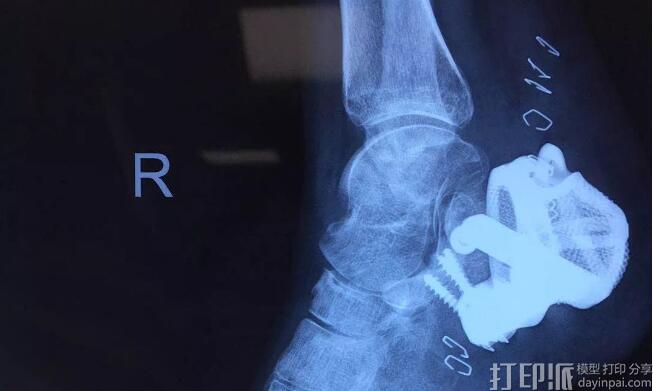

由铂力特打印、东望科技出品的金属3D打印跟骨在咸阳市第一人民医院成功完成植入手术;经过术后3个月的恢复与疗养,跟骨缺损患者各项体征正常,假体稳定植入,现逐步脱离拐杖进行行走训练。这是咸阳地区首次完成个性化金属3D打印植入物手术,填补了其地区的3D医疗空白。

跟骨假体

尺寸:50×45×35mm

重量:40g

材质:钛合金